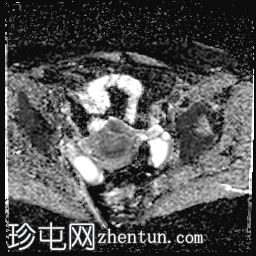

轴位T1加权像

增强脂肪抑制像

可见膀胱左侧壁有一边界清晰的T2低信号实

性病

灶,无扩散受限,均匀强化。未见膀胱周围侵犯或肾积水。

子宫底部前壁可见一小肌瘤。双侧卵巢可见无强化囊肿。盆腔及腹股沟未见异常淋巴结肿大。

这是一例经组织学证实的膀胱平滑肌瘤病例。